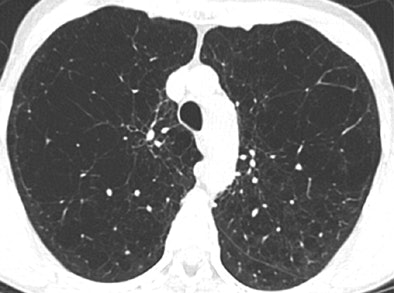

| Axial CT scans in two subjects with different COPD phenotypes: emphysema-predominant COPD (≥ 35% emphysema, <1.75-mm segmental bronchial wall thickness) (above) and airway-predominant COPD (<35% emphysema, ≥ 1.75-mm segmental bronchial wall thickness) (below). Images republished with permission of the Radiological Society of North America, from Radiology, July 25, 2011, 110173. |

In addition, while many patients had a mixture of structural changes related to their COPD, two subgroups predominantly with emphysema or large airway disease could be identified.

Patients with more than 35% emphysema volume and wall thickness greater than 1.75 mm had a higher COPD exacerbation frequency than did the subjects with less than 35% emphysema and a wall thickness of less than 1.75 mm.

The less-severe patients in both groups reported experiencing a mean of 0.62 exacerbation per year, compared with means of 1.1 exacerbations per year reported by the emphysema-predominant group (p < 0.0001) and 0.8 exacerbation per year reported by the airway-predominant group (p = 0.07).